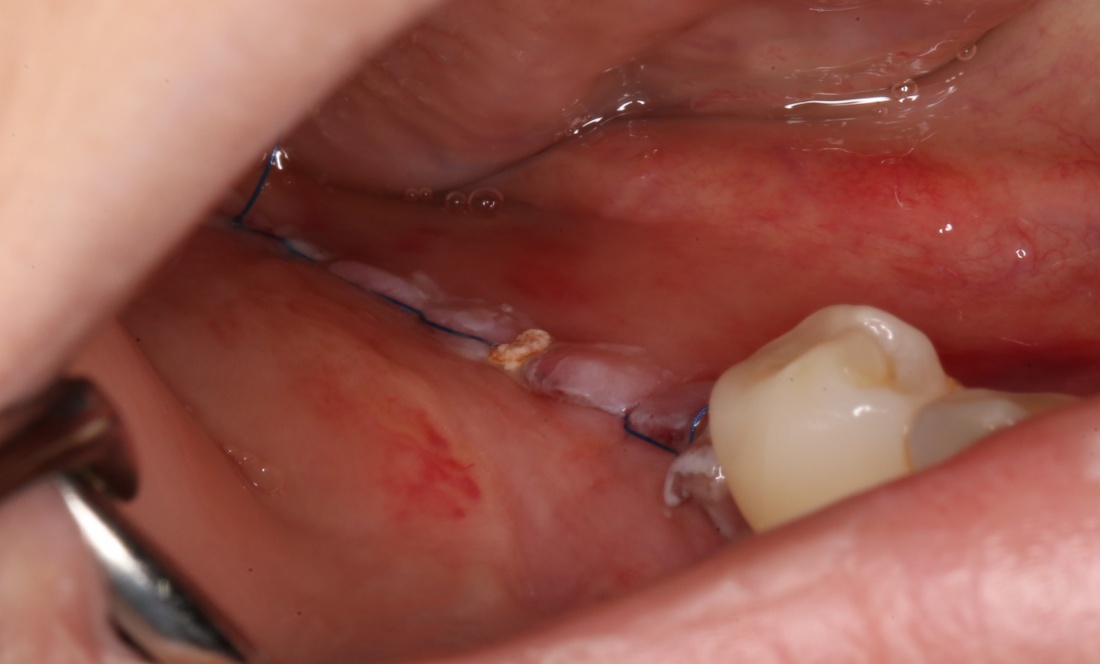

Наложение швов.

Если на этапе разреза и формирования раны всё сделано правильно, то наложение швов не вызывает особых трудностей. Периостотомия или послабляющие разрезы на периосте не требуются (ни практически никогда не требуются). А сами швы получаются аккуратными и герметичными:

Обрати внимание, что все шовные лигатуры находятся в пределах кератинизированной десны. Это позволяет избежать деформации тканей и лишних рубцов. В наиболее уязвимых местах (около зубов) шовные лигатуры лучше продублировать.

Если бы мне пришлось делать это сейчас, то я бы использовал непрерывный «матрацный» шов. Он удобнее, быстрее в наложении и комфортнее для пациента. Минус — если распускается, то распускается весь. К тому же, его очень неудобно снимать.

Несмотря на то, что уже тогда мы широко использовали непрерывные швы в подобных случаях, здесь я, во-первых, зассал (может распуститься), во-вторых, снятие швов предполагалось в поликлинике по месту жительства пациентки, и мне не хотелось, чтобы там при снятии швов начудили. Как выяснится позже — зря беспокоился.

Неизменно одно — в таких операциях мы использовали и до сих пор используем нерезорбируемые монофиламентные шовные материалы, поскольку они наиболее гигиеничные. Чтобы острые концы нитей не беспокоили пациента, их можно оплавить нагретой гладилкой или гуттаперчевым плаггером.